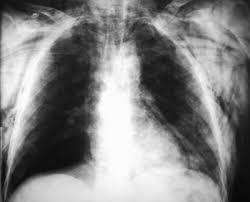

¿ A QUÉ TIPO DE SISTEMA DE RESPIRACIÓN HACE REFERENCIA LA SIGUIENTE IMAGEN ?

Answer

• TRAQUEAL

• BRANQUIAL

• PULMONAR

• CUTÁNEA

• FOTOSINTESIS

• DIFUSIÓN SIMPLE